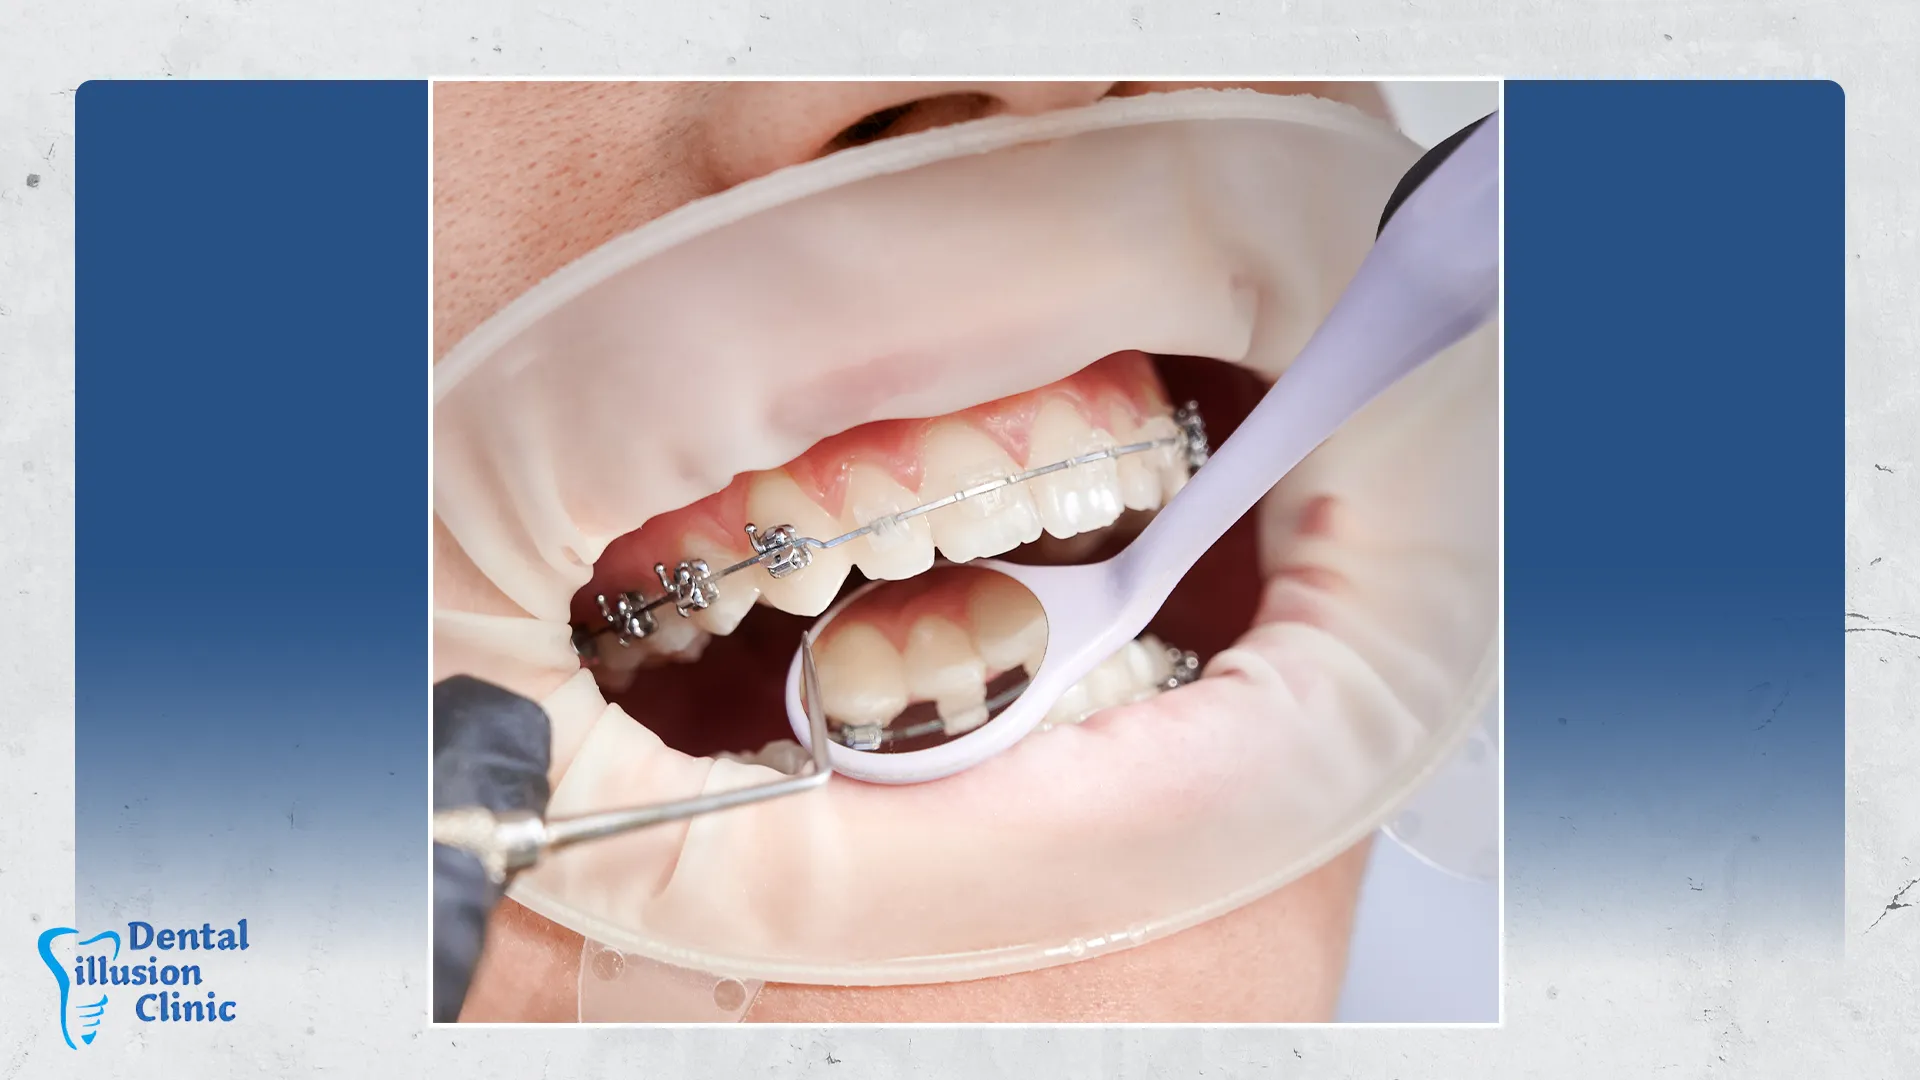

تعتمد عملية حشو الأسنان على خطوات دقيقة تبدأ بإزالة التسوس وتنظيف التجويف المصاب بعناية، ثم إعادة ملئه بأحد المواد المناسبة مثل الكومبوزيت، أو الأملغم، أو السيراميك، وفقًا لحالة السن ومكانه. كما يتم الاهتمام بتناسق الحشوة مع لون وشكل الأسنان الطبيعية، مع ضمان قوة التحمل والثبات للحصول على نتائج فعالة ومظهر جمالي يدوم طويلاً.